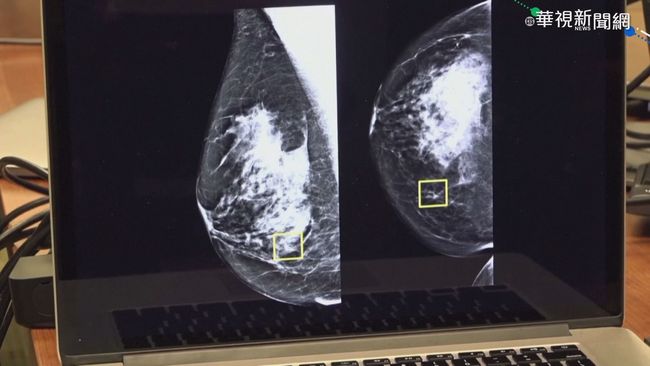

黃醫師特別說明,雖然九成乳房腫塊屬於良性,包括纖維囊腫、水泡或發炎,但一般人難以自行分辨。當腫塊大到能觸摸時,通常已接近2公分。若發現不會痛的硬塊且月經過後仍持續存在,或在腋下發現任何大小的硬塊,都必須高度警覺盡速就醫。乳房纖維囊腫常見於30至50歲女性,雖屬良性但可能與乳癌同時存在,不可輕忽。